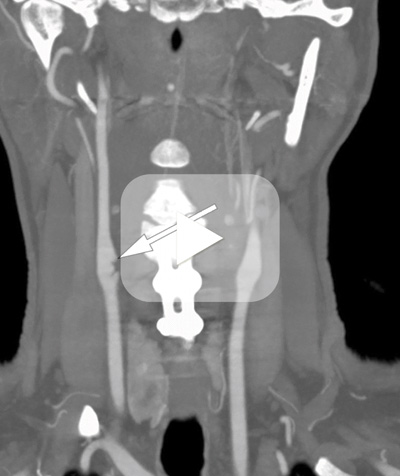

Først to år etter første hjerneinfarkt viste ny ultralydundersøkelse av høyre a. carotis interna en pendulerende, veggtilheftet masse (video) som med pulsativ bevegelse inn i lumen ga intermitterende stenose på rundt 60 % . Funnet ble også sett på CT-angiografi, som viste veggforandringer (bilde kun i nettutgaven). Ved sammenlikning av flere CT-angiografiske undersøkelser så man leieendring av carotiskar på høyre side. Veggforandringens utseende var ikke typisk for arteriosklerotiske plakk, idet det var en enslig fokal lesjon som protruderte inn i lumen med membranliknende seil (bildet).